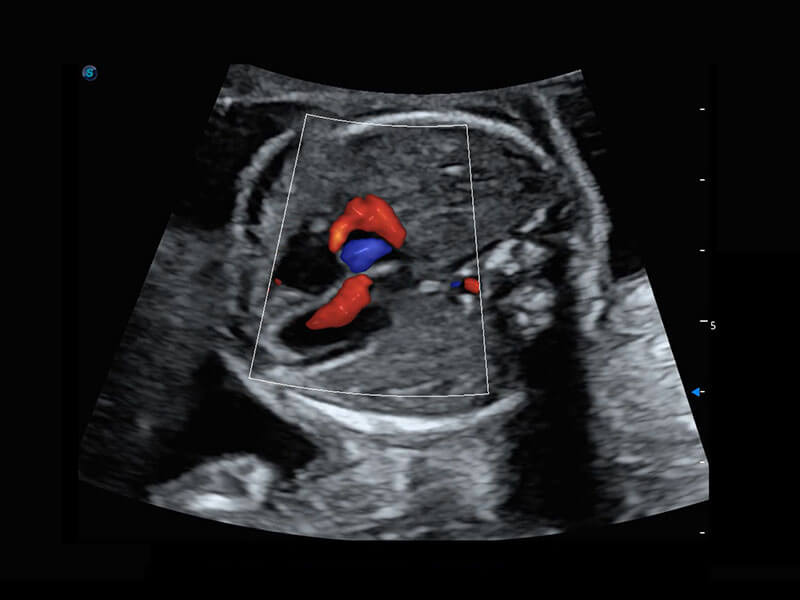

P60在胎兒早孕期超聲篩查中為您帶來優(yōu)異的圖像質(zhì)量。

早孕-胎心